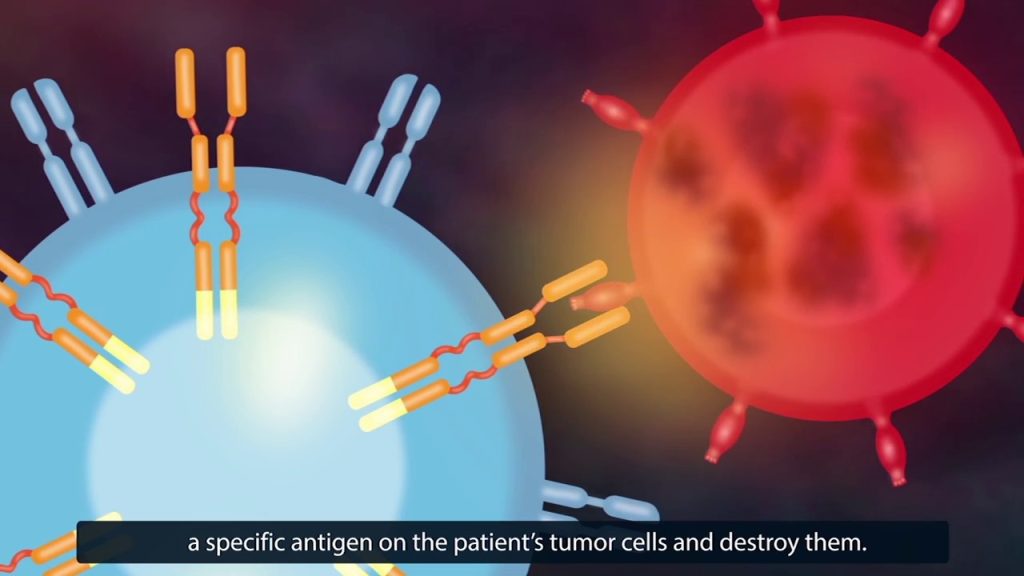

كانت الخطوة الأولى لتطوير علاج السرطان الفردي هي العلاج المستهدف. يشمل العلاج المستهدف استخدام العقاقير أو اللقاحات، والتي يتم توجيه نشاطها إلى أنواع محددة بدقة من الخلايا السرطانية. على وجه الخصوص، أثبت نفسه في الدراسات السريرية دواء Glivec (الاسم الدولي – Imatinib) و Herceptin (الاسم الدولي – Trastuzumab). وتشمل هذه الأدوية الأجسام المضادة وحيدة النسيلة لمكونات محددة في خلايا السرطان الموجودة لدى المريض. بسبب خصوصية العمل العالية للأجسام المضادة، تهاجم المستضدات خلايا الأورام وتدمرها دون التأثير على الأنسجة والأعضاء السليمة.

- إنشاء الخلايا الليمفاوية مع مستقبلات المستضدات الخيمرية (chimeric antigen receptor, CAR). في هذه الحالة، بمساعدة تقنيات الهندسة الوراثية، يتم إنشاء مستقبلات خاصة تتطابق بشكل مثالي مع الخلايا السرطانية للمريض. بعد ذلك، يتم وضع المستقبلات على الخلايا الليمفاوية للمريض، والتي تبدأ في التكاثر بنشاط والقتال مع نسيج الورم.

CAR – جزيئات صناعية مصممة بعناية لا توجد في البيئة الطبيعية. الغرض من إنشاء CAR هو مهاجمة الجزيئات المستهدفة الخاصة على سطح الخلايا السرطانية. هم عادة المستضدات CD19 و CD22، وهي مخصصة للخلايا الخبيثة في سرطان الدم. من المهم للغاية عدم وجود جزيئات مماثلة على سطح الخلايا السليمة. في تلك الحالة ستخضع الخلايا السليمة أيضاً للهجوم، مما يقلل من تأثير العلاج.

لدى الجزيء CAR بنية معقدة. كل جزء من المستقبلات الخيمرية، أو كل دومين، له أهميته في تحقيق النتيجة النهائية – تدمير الخلايا السرطانية.

يتكون CAR من الأجزاء التالية، بدءاً من السطح:

دومين التعرف على المستضد، والدومين المستهدف ((antigen recognition [targeting] domain). مهمة هذا الجزء من CAR هو البحث عن الخلية السرطانية وتحديدها بدقة. من الناحية المجازية، يطابق مستقبل CAR الجزيئات الموجودة على سطح الخلية السرطانية كما يطابق المفتاح القفل. إذا كان مثل هذا “المفتاح” مفقودًا، تتوقف الخلايا المناعية عن رؤية الخلايا السرطانية. هذا يسمح لعملية الأورام بالتقدم دون حسيب أو رقيب.

- في الممارسة السريرية، يتم تطبيق CAR على المستضدات CD19 و CD22. لمزيد من الدقة في العلاج، يتم إنشاء CAR التي يمكنها التعرف على العديد من المستضدات في نفس الوقت.